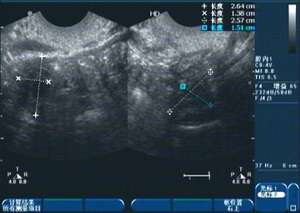

1、診斷:醫(yī)生會(huì)通過詢問病史、體檢及輔助檢查(如超聲檢查、激素檢測(cè)等)來(lái)確定診斷。